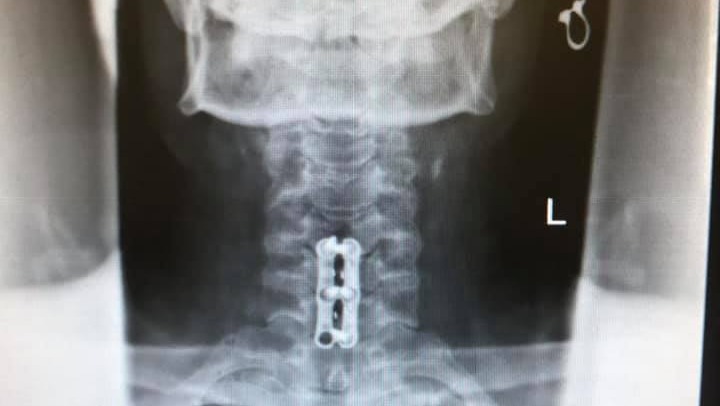

Hi All, my name is Kirsten and I live in Fort Wayne, Indiana. In early 2020 my dad John was riding his motorcycle in Key West, Florida where lives, and he went to stop and say hello to a friend he spotted but little did he know that a construction crew had left a 9" hole in the road partially uncovered exactly where he was about to put his foot down. This construction oversight caused him to lose balance and try to catch himself while his 700lb. touring bike to landed on top of him. He's undergone neck, back, knee, and elbow surgeries and still has more to go. Everything is also a bit more complicated for him because he lives on a boat by himself, aside from his best mate, his cat Mate.

I’ve been the helper most of my life! My life was flipped 180 with a motorcycle accident going zero mph and no one else involved. Had back, neck, left elbow n right knee. More needed ASAP but I’m tapped out.